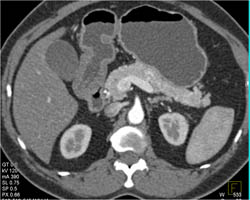

Splenic Artery Aneurysm Simulates A GIST Tumor